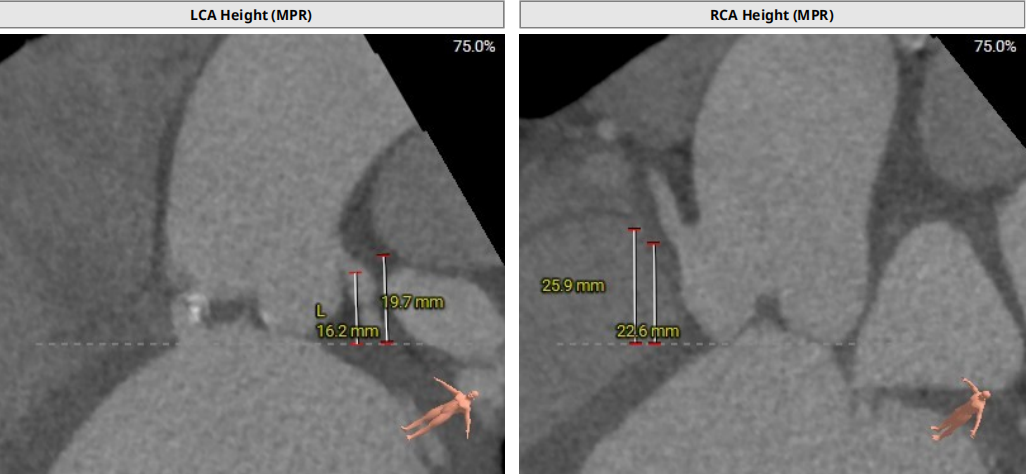

术前CT评估示

术前CT评估

三叶瓣,轻中度钙化,瓣叶增厚。

舒张期图像评估:瓣环面积约741mm²,折算瓣环直径30.7mm,LVOT约958mm²,折算直径34.9mm。SOV:36.5*35.1*38.7mm,窦部空间足够,瓣叶长度适中,瓣叶增厚,STJ:28.8(H)* 38.1mm (D),STJ直径和高度风险低。LCA:16.1mm,RCA:22.6mm,瓣叶长度适中,窦部空间足够,瓣环夹角60°。

模拟29mm瓣膜植入情况:

血管入路评估:入路两侧分叉高度适中,穿刺点位置尚可,直径尚可,穿刺点附近未见钙化,右侧最小均径10.2mm,左侧最小均径约9.1mm,16F可扩张鞘能顺利通过;建议右侧为主入路。

三叶瓣,瓣环面积约578.0mm²,折算瓣环直径27.1mm,LVOT约618.8mm²,折算直径28.1mm,SOV:46.1*42.9*43.4mm,窦部空间较大,瓣叶长度适中,瓣叶明显增厚,STJ:32.3(H)* 43.1mm (D),STJ直径和高度足够;LCA:22.6mm,RCA:22.9mm,瓣叶长度适中,窦部空间足够;瓣环夹角53°。

血管入路评估:血管穿刺位点直径可,腹主动脉-降主动脉段接近90°迂曲。